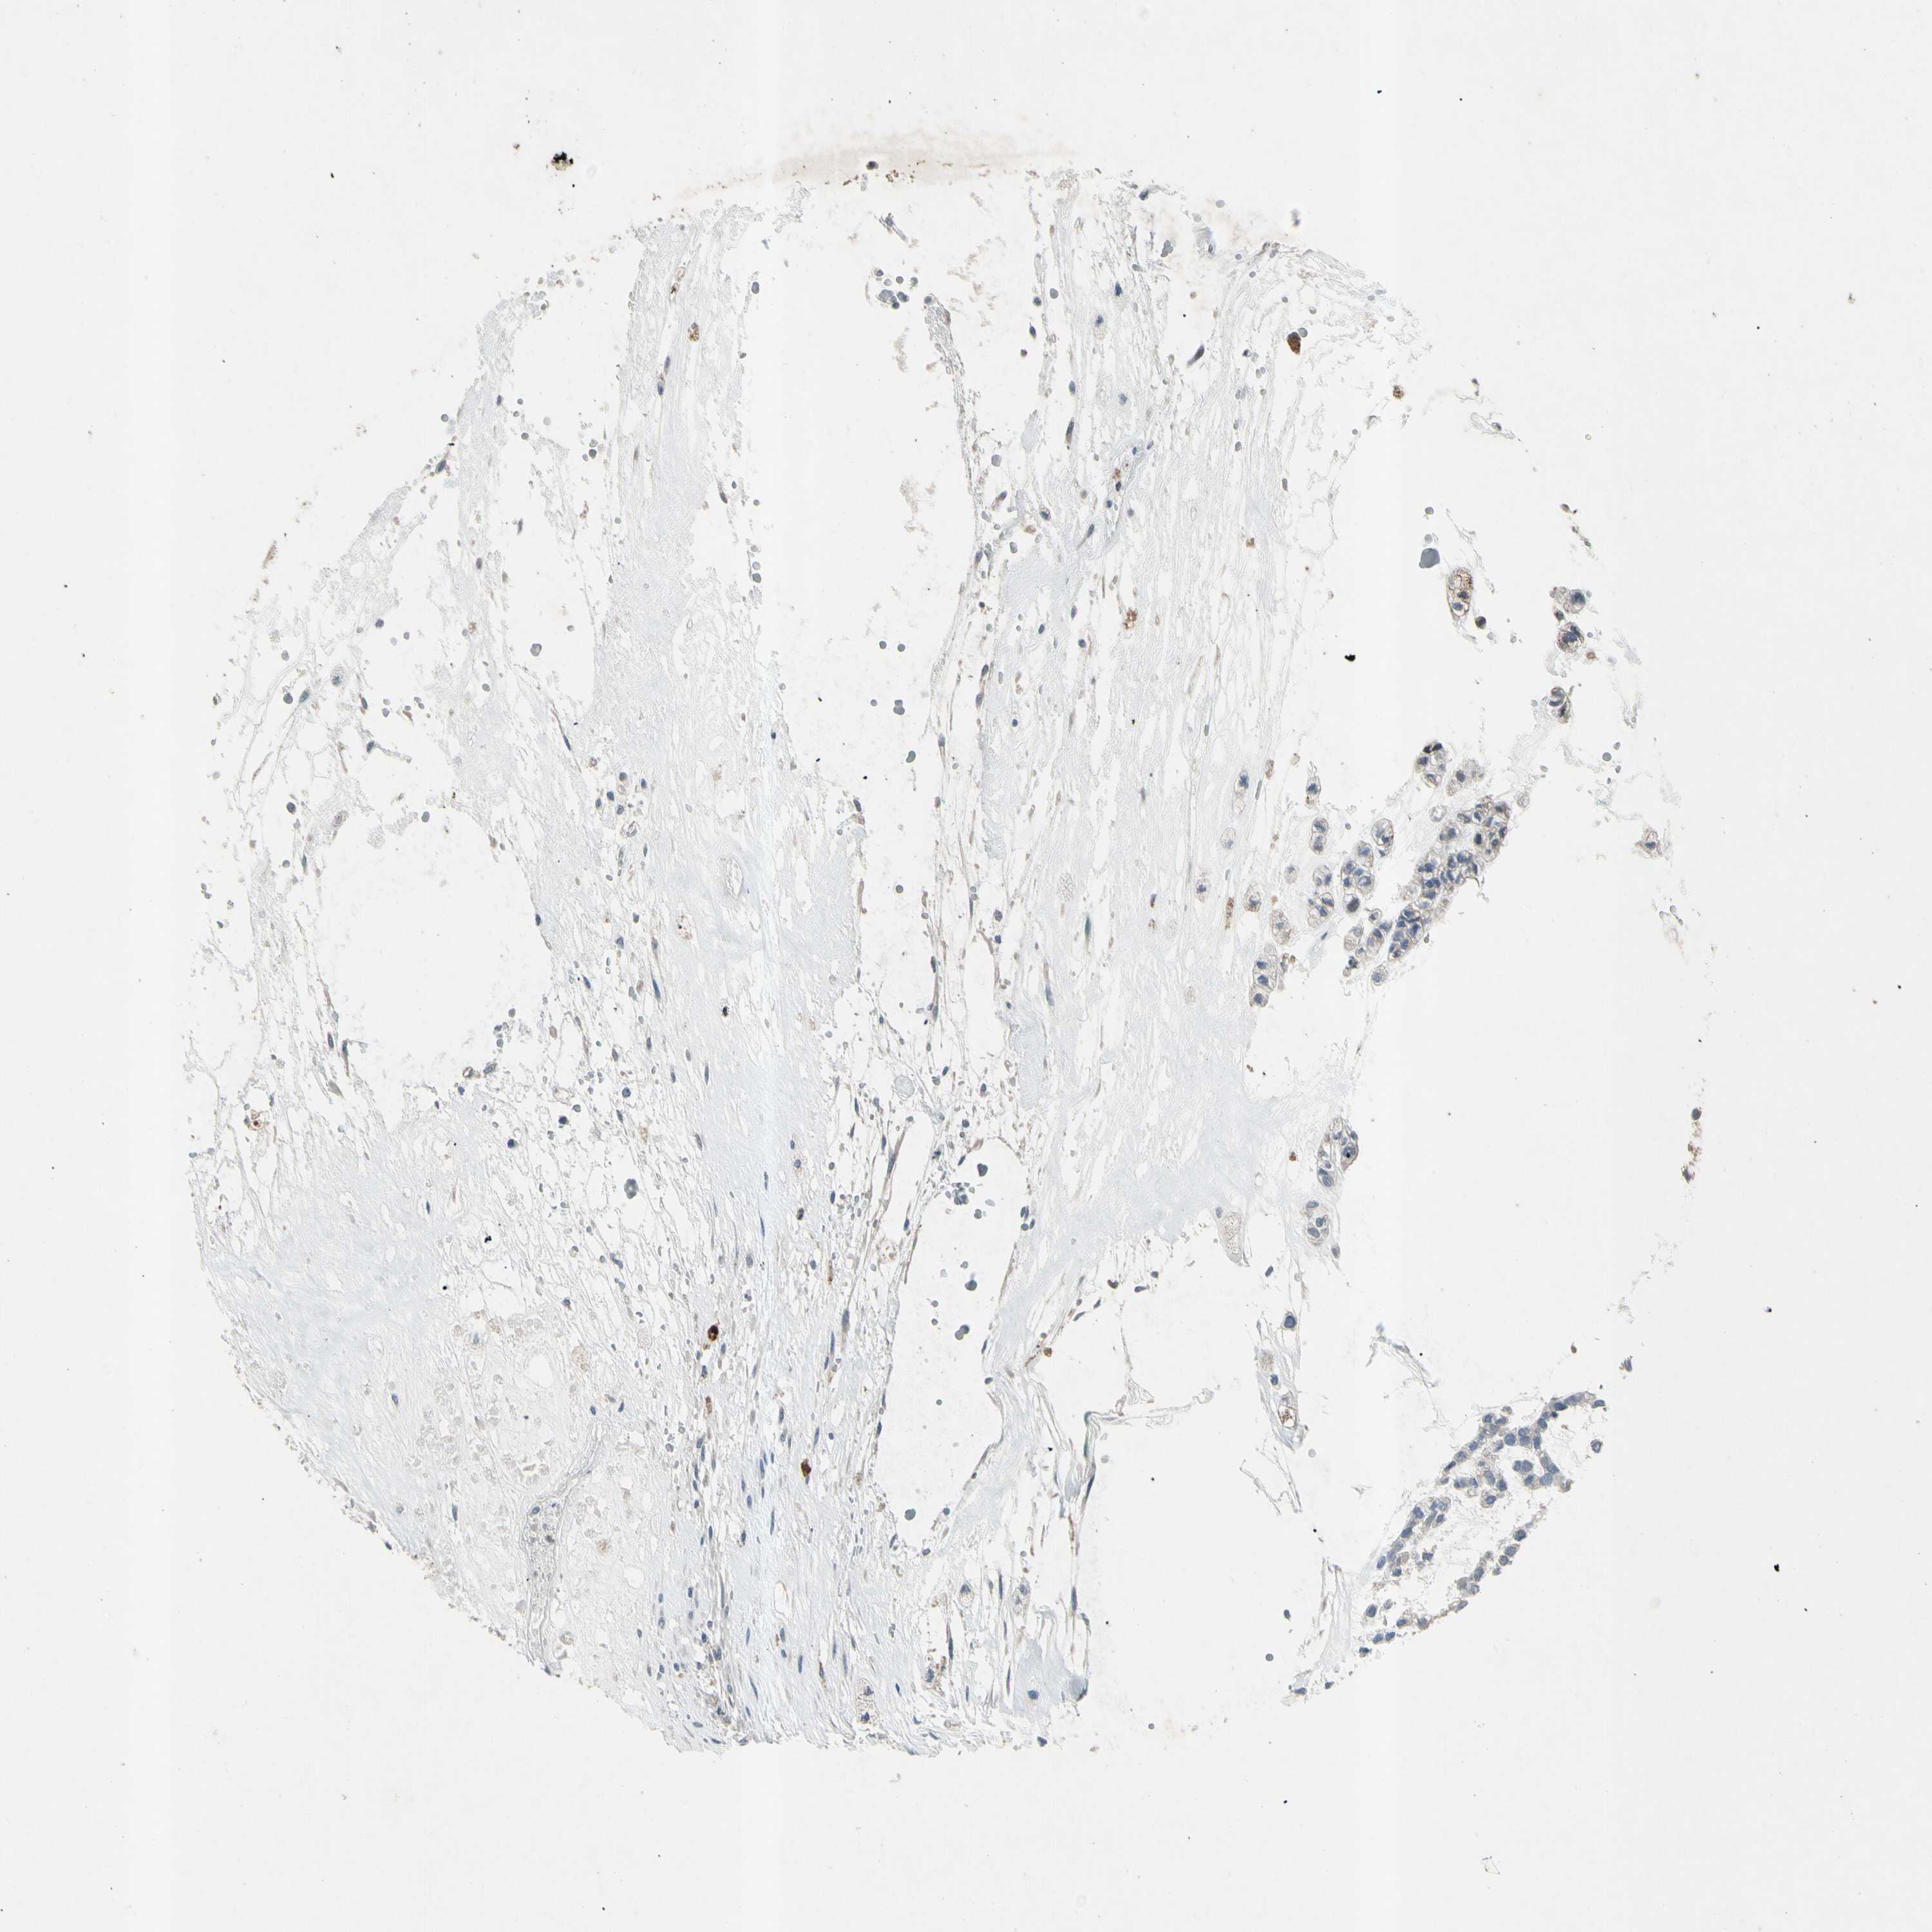

HEAD AND NECK CANCER - Protein expressioni

A mouse-over function shows sample information and annotation data. Click on an image to view it in a full screen mode. Samples can be filtered based on level of antibody staining by selecting one or several of the following categories: high, medium, low and not detected. The assay and annotation is described here.

Antibody stainingi

Antibody staining in the annotated cell types in the current human tissue is reported as not detected, low, medium, or high, based on conventional immunohistochemistry profiling in selected tissues. This score is based on the combination of the staining intensity and fraction of stained cells.

Each image is clickable and will lead to virtual microscopy that enables deeper exploration of all samples and also displays staining intensity scores, fraction scores and subcellular localization as well as patient and tissue information for each sample.

Antibody HPA008588

Squamous cell carcinoma, NOS

Squamous cell carcinoma, metastatic, NOS

Adenocarcinoma, NOS

Adenoma, NOS